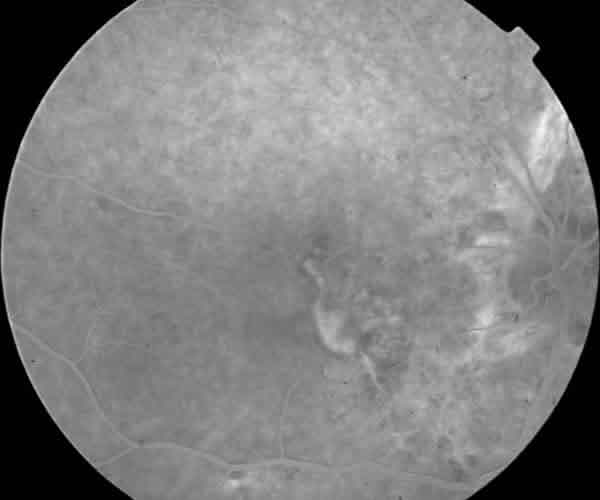

A la exploración presentaba una agudeza visual de 0,1 en ojo derecho y movimientos de mano a 1 metro en ojo izquierdo, medios refringentes transparentes y presión intraocular de 16 mmHg en ambos ojos. En fondo de ojo derecho se apreciaban múltiples hemorragias subretinianas en polo posterior y a nivel nasal, asociadas a una imagen blanca lineal irregular, de trayecto vertical que atravesaba el área macular, compatible con una rotura coroidea (fig. 1). El ojo izquierdo mostraba una cicatriz disciforme sin aparentes variaciones respecto a su situación previa (fig. 2). En ambos ojos eran evidentes las estrías de color marrón-anaranjado peripapilares extendiéndose de forma radial a la periferia. La angiografía fluoresceínica (AGF) mostró un patrón hiperfluorescente por defecto ventana a nivel de las estrías y la rotura, con bloqueo de la fluorescencia por efecto pantalla a nivel de las hemorragias subretinianas (fig. 3).

Fig. 1.

Fondo de ojo derecho. Hemorragias subretinianas en polo posterior y a nivel nasal, asociado a rotura coroidea que atraviesa área macular. Estrías angioides peripapilares.

Fig. 3. AGF ojo derecho. Patrón hiperfluorescente de las estrías y a nivel de la rotura coroidea. Hipofluorescencia a nivel de las hemorragias subretinianas.